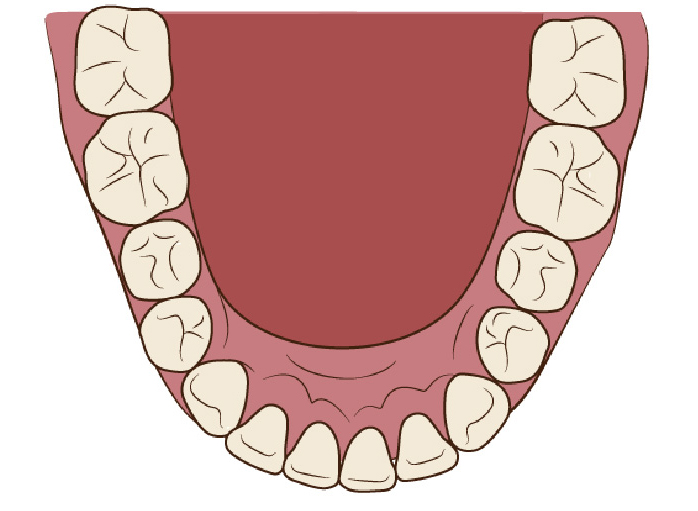

狭い歯列(狭窄歯列)によって、舌が歯列の中に収まらない状態です。

●高口蓋 ●低位舌 ●口呼吸

狭窄歯列(高口蓋)

狭窄歯列(低口蓋)

狭窄歯列(低位舌)

右のように、狭窄歯列だと舌は、狭い歯列に阻まれて、前方や上方の口蓋に自由に動くことができません。その結果、舌は低い位置(低位舌)にあり、前方に出ず後方に位置するので、気道が狭くなってしまっています。

一方、左のように、広い歯列だと舌は、前方にも上方にも自由に動けるので、舌は普段は口蓋についていて鼻呼吸が無理なくできているのです。

舌が正常な位置にある

舌が低い位置にある

舌の正しい位置

正しい位置

低い位置

狭い歯列(狭窄歯列(きょうさくしれつ))

高口蓋(上顎が深い→鼻腔が狭い)

舌が歯列に納まらない→低位舌

歯並びが悪い

かみ合わせが悪い